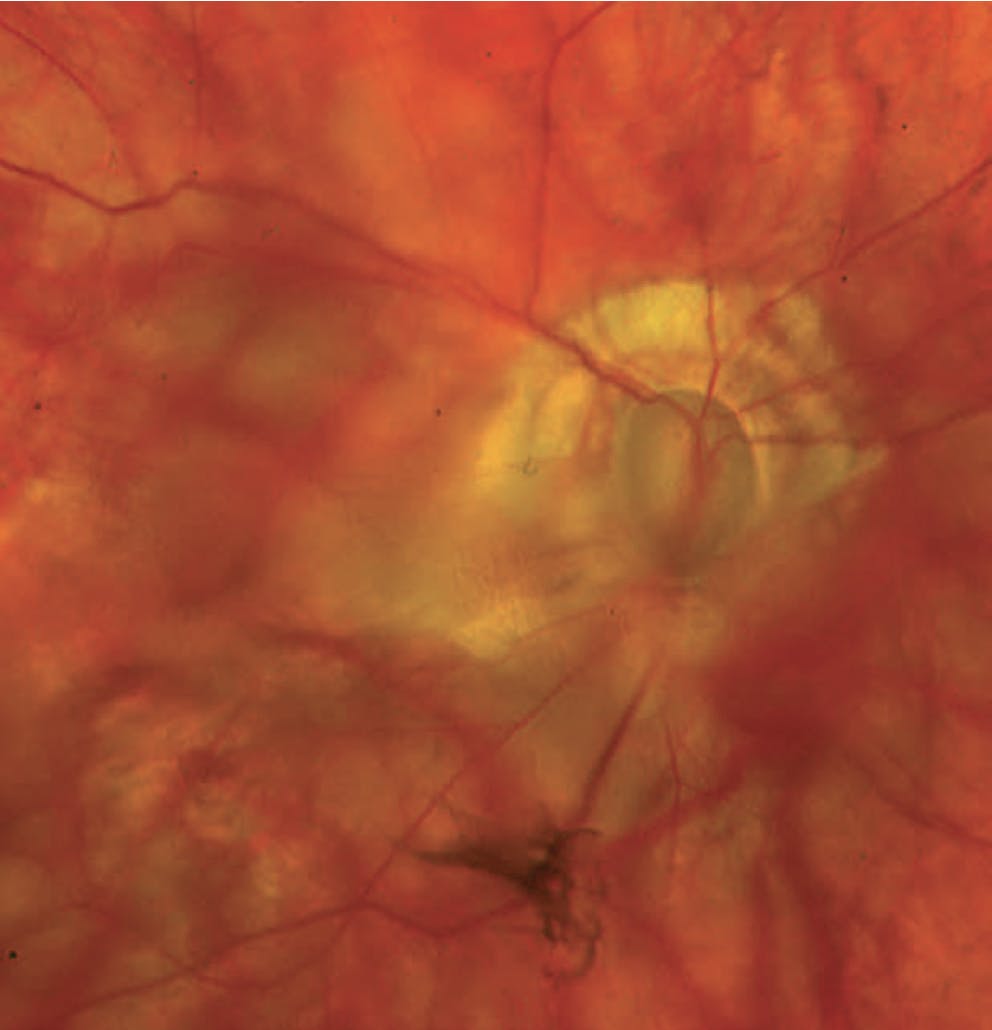

A slit-lamp examination reveals a moderate nuclear sclerotic cataract and iris transillumination defects but no posterior bowing, consistent with a patent iridotomy. The trabecular meshwork shows minimal pigmentation, and no Krukenberg spindle is evident. Marked cupping of the optic disc is observed; the cup-to-disc ratio is 0.9, and there is significant peripapillary atrophy (Figure 1). Corneal hysteresis is 6.4, suggesting that the true IOP may be higher than the measured IOP.

Figure 1. Fundus photography shows marked cupping, peripapillary atrophy, and media opacity from a cataract.